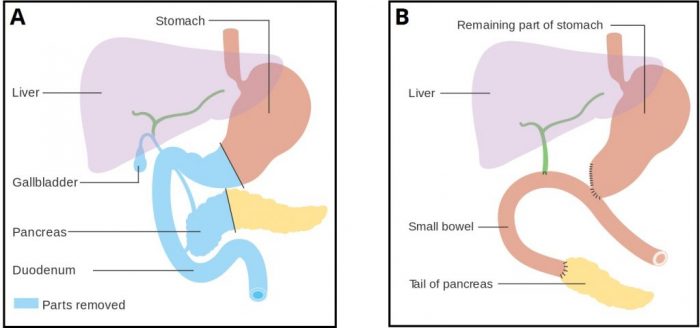

When I was sixteen, they finally had a surgery for him. It’s called the Whipple. It’s one of those surgeries where you’re almost better off just dying. They remove your duodenum, your gallbladder, part of your stomach, part of your pancreas, and then stitch what’s left back together. Without a gallbladder, you can’t process fat, so bacon is out. With a severely maimed pancreas, you’re pre-diabetic at best, if your pancreas doesn’t just give up and you become diabetic immediately. And with no colon, your very short intestines develop Short Bowel Syndrome, where you just don’t have enough guts to absorb your food properly. The surgery takes 12 hours and you have a 60% chance of just dying right there on the table. Half of those who survive it die within a month of the surgery; my biological grandmother was one of those people. We were prepared for my father to die; my grandmother and my aunt flew up from Nova Scotia to see him, to be there in case there was a funeral.